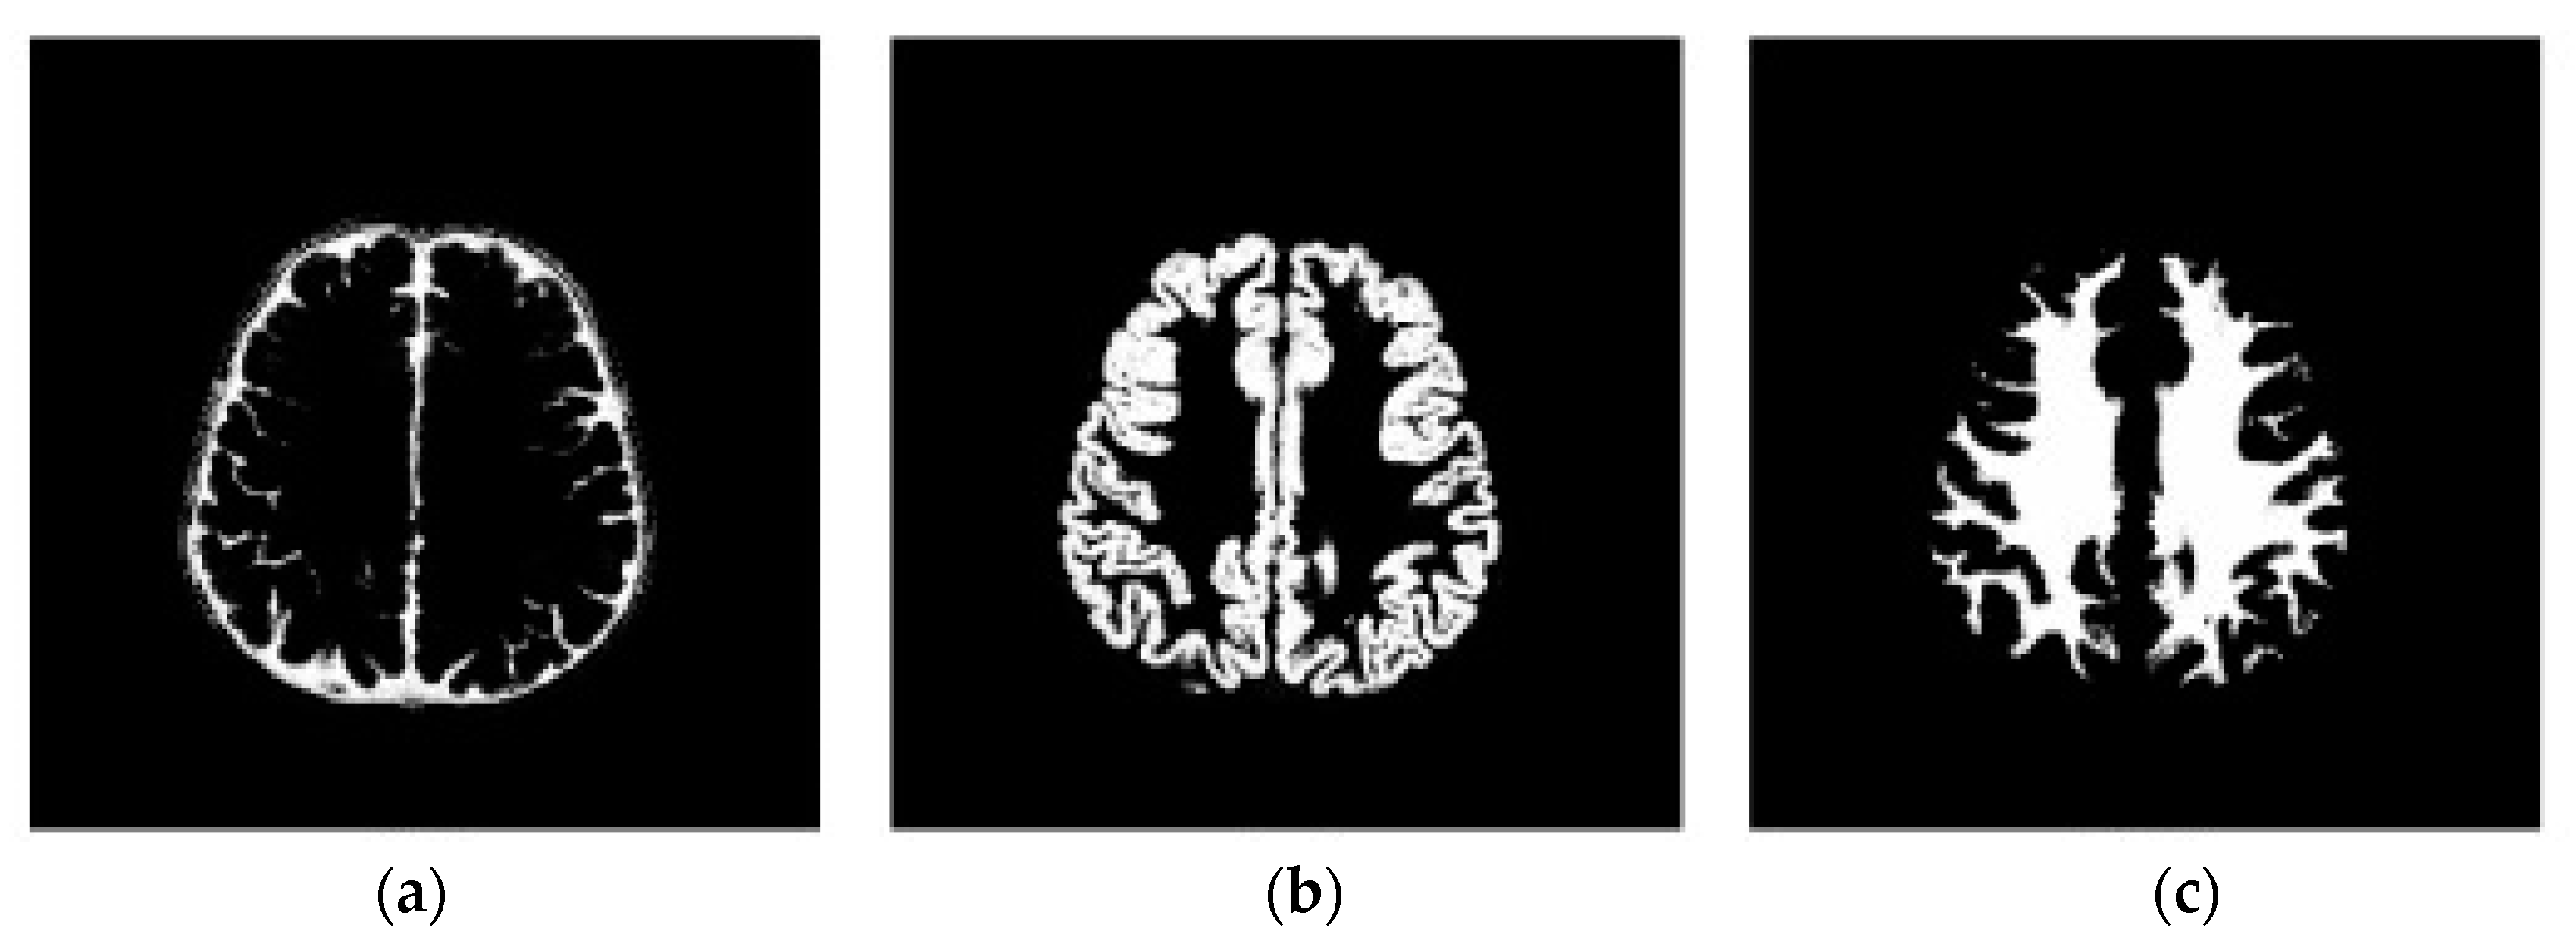

3.2. Step 2 Quantum Dragonfly-Based Clustering Phase

3.2.1. Initial DA’ Food Sources Extraction Using K-Mean Algorithm

3.2.2. Determine Initial Contour Points Using Quantum Dragonfly Algorithm